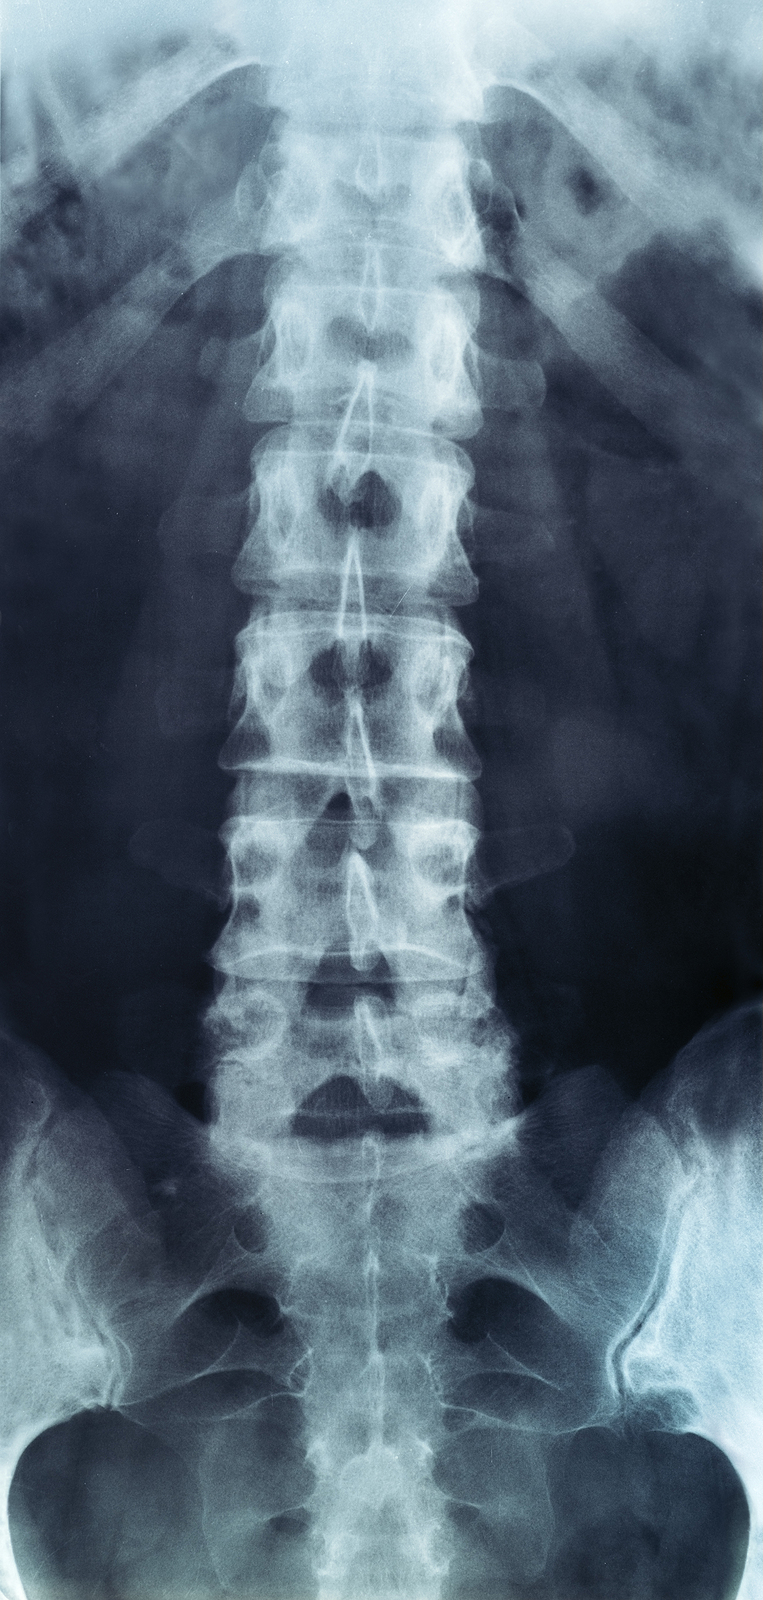

The human spine is made up of 24 spinal bones, called vertebrae, as well as the sacrum and the coccyx. The sacrum is a triangular bone near the bottom of the spine and the coccyx is more commonly known as the tailbone.

Vertebrae are stacked on top of one another to create the spinal column. The spinal column gives the body its form and helps sustain an upright position.

The lumbar spine—where pain is often experienced—is made up of five vertebrae positioned near the bottom of the spinal column. Doctors often refer to these vertebrae as levels L1, L2, L3, L4 and L5. The ‘L’ refers to ‘lumbar’. The lowest vertebra, L5, is connected to the top of the sacrum—a triangular bone at the base of the spine that is located between the two pelvic bones. Some people are born with an extra or sixth lumbar vertebra called L6. Having an extra vertebra doesn't usually cause physical problems.

X-rays are usually the first test ordered before any of the more specialized tests are completed. X-rays use electromagnetic radiation to show problems with bones and can also reveal problems such as fractures, infections, or bone tumors. X-rays of the spine can give your doctor information about bone alignment and can demonstrate how much degeneration has occurred in the spine. Both alignment and degeneration can affect the amount of space in the neural foramina and between the discs, which subsequently impacts the nerves in the area. This is important information your health care professional can use to establish a treatment plan.

Flexion and Extension X-rays